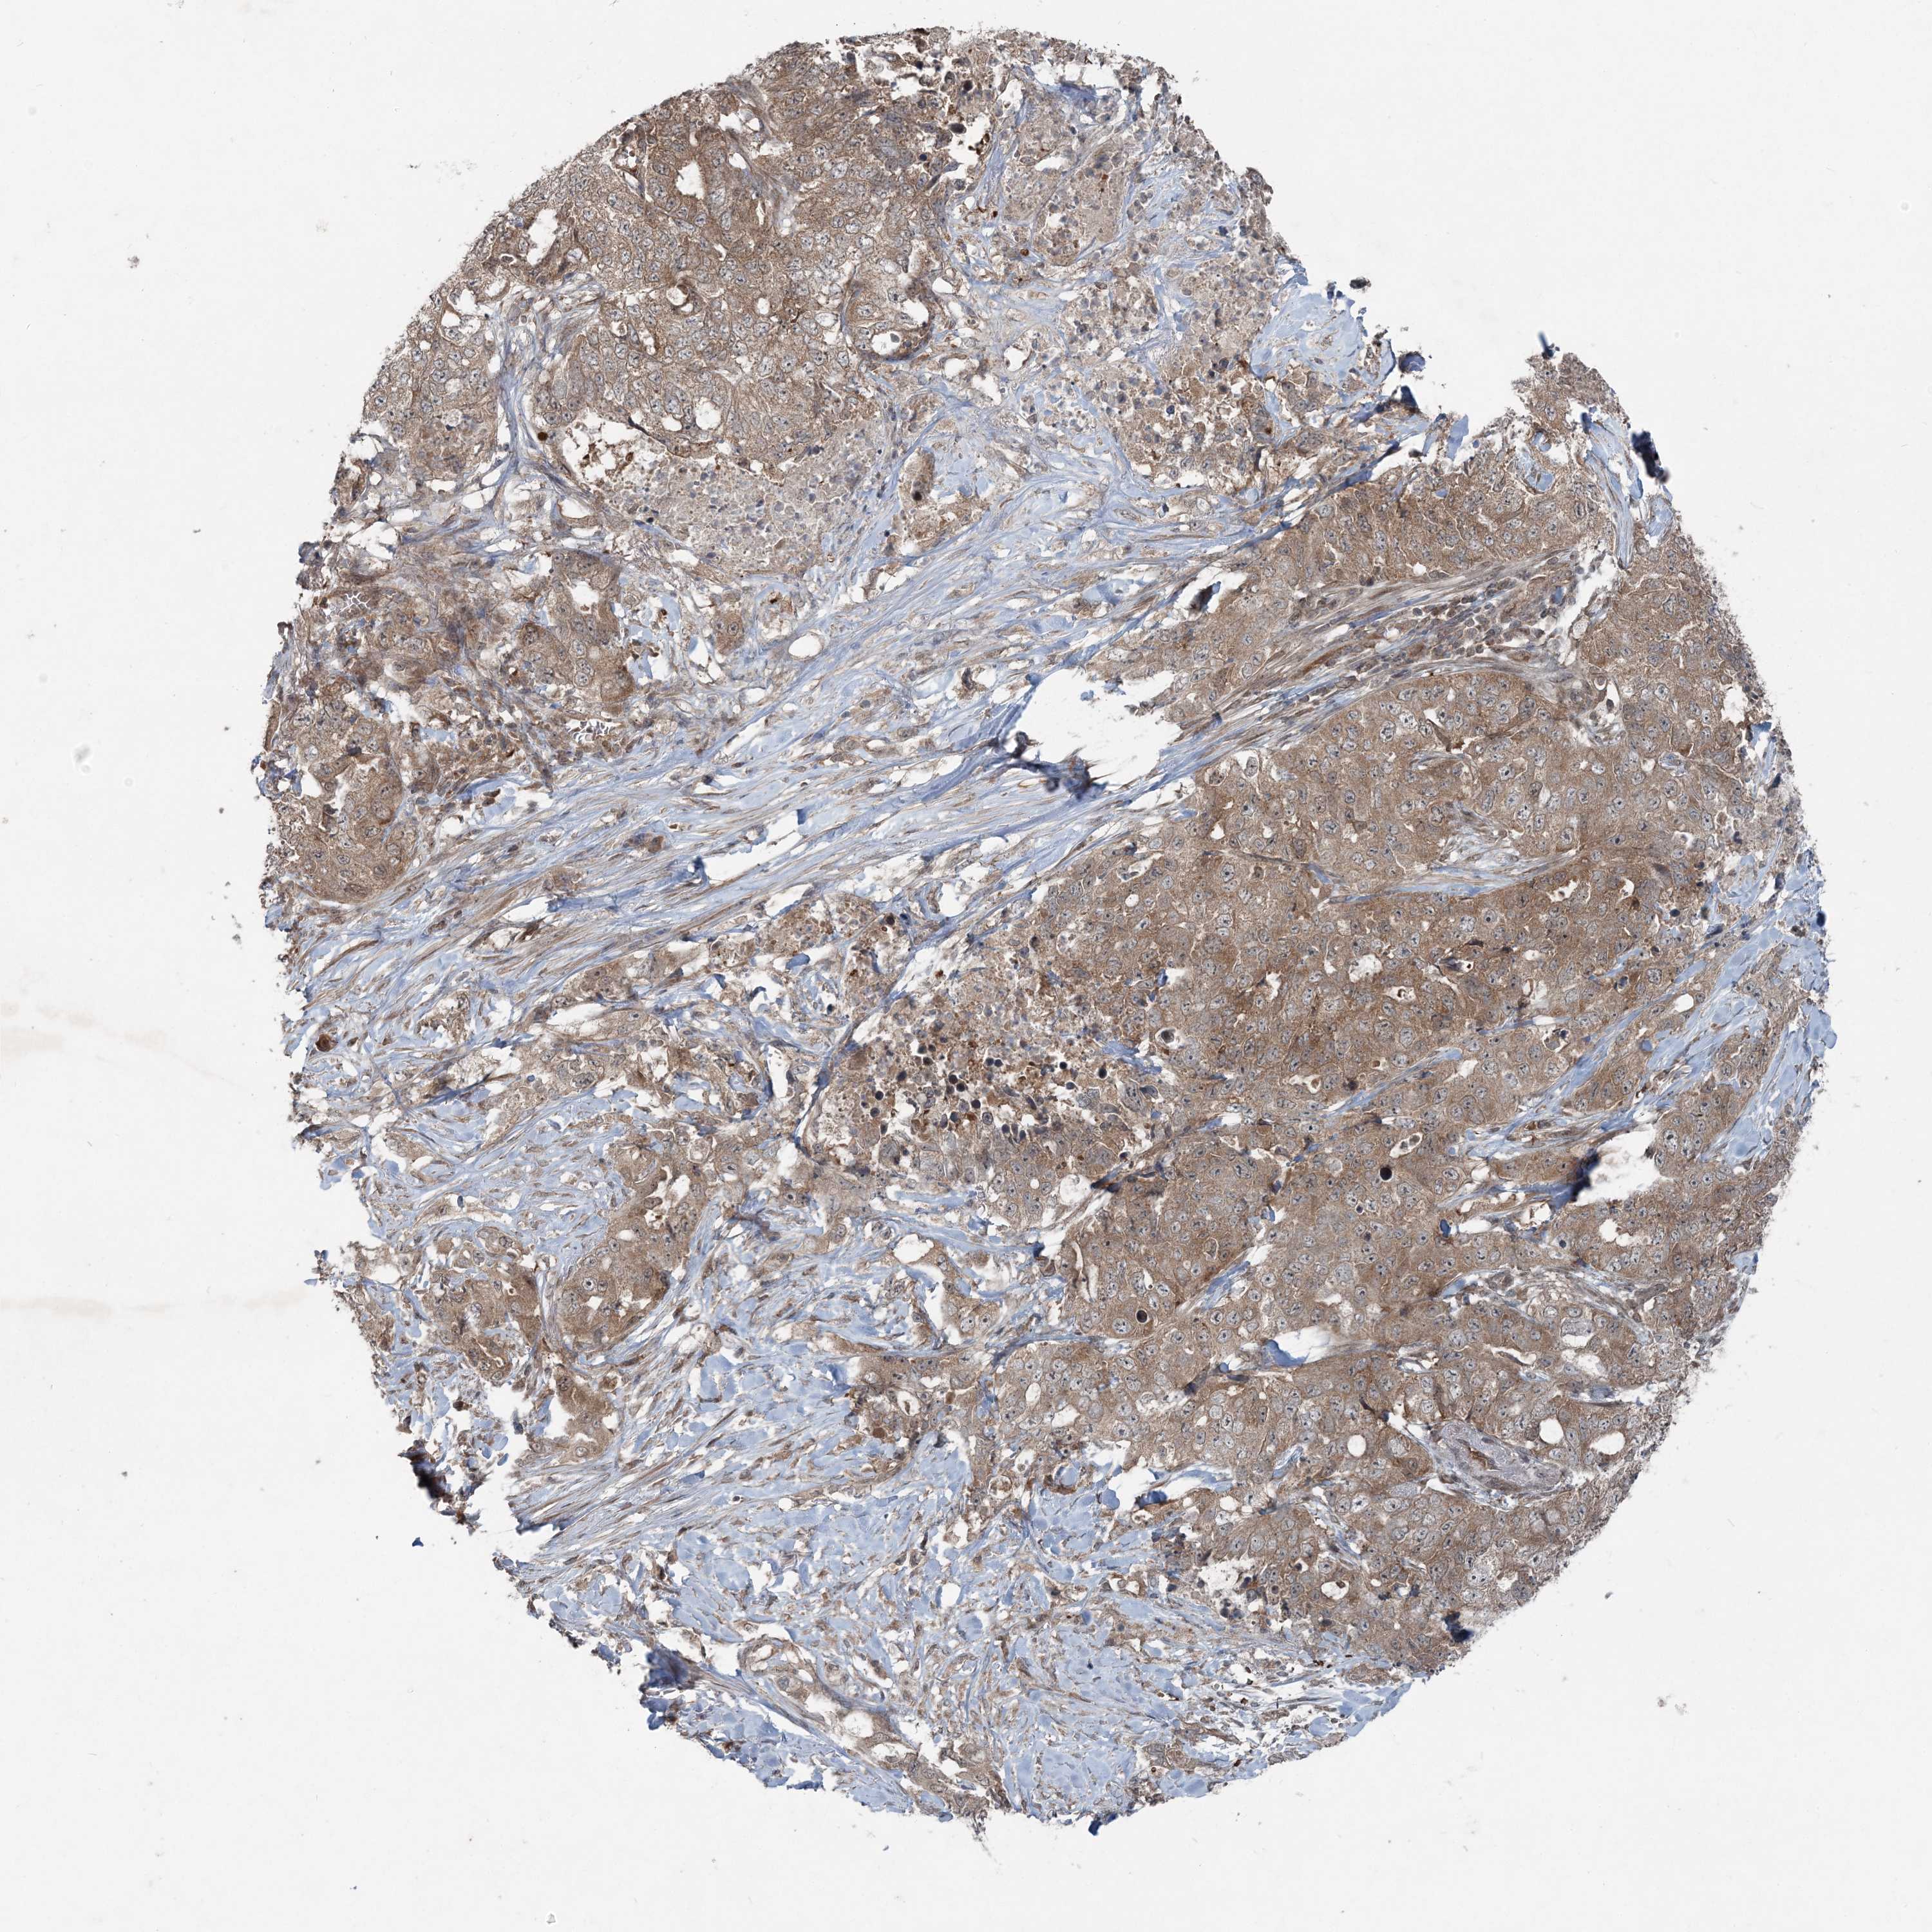

CANCER LUNG CANCER Show tissue menu

LUAD TCGA LUAD VALIDATION LUSC TCGA LUSC VALIDATION PROTEIN LUAD CPTAC PROTEIN LUSC CPTAC PROTEIN EXPRESSION

ANTIBODIES

AND

VALIDATION